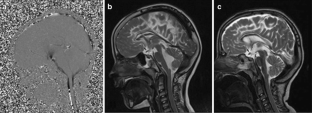

Fig. 1